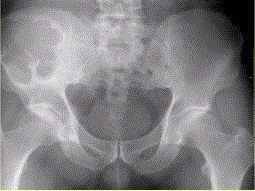

患者男,28岁,右下腹及臀部疼痛5个月余。查体:右髂骨外后侧压痛,右下腹可触及一软组织包块,质韧,固定。行骨盆正位CR、骨盆CT及MR扫描见下图。...

问题 患者男,28岁,右下腹及臀部疼痛5个月余。查体:右髂骨外后侧压痛,右下腹可触及一软组织包块,质韧,固定。行骨盆正位CR、骨盆CT及MR扫描见下图。 关于病变发生的部位,叙述正确的是

选项 A.右髂骨皮质部,累及右侧腰大肌 B.右髂骨髓质部,累及右髂骨皮质及右侧腰大肌 C.右侧腰大肌,累及右髂骨 D.盲肠,累及右髂骨 E.末段回肠,累及右髂骨

答案 B